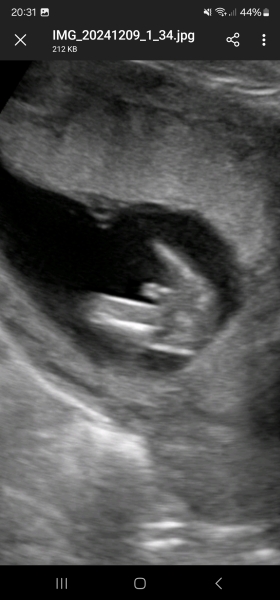

Mlif · 16/12/2024 13:52

Hey I had a scan at 14 weeks. Does this look like a baby boy or isit the umbilical cord between the legs...